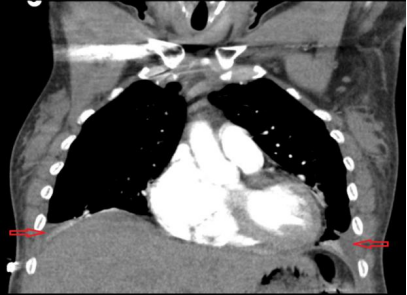

(1) 下肢B超:检查结果排除深静脉血栓形成(2)心电图:显示为窦性心律,存在 R 波递增不良(QTc 485ms)(图1),可排除急性冠脉综合征;(3)胸部 X 线(入院时):可见双侧斑片状阴影及双侧胸腔积液(图2);(4)病原学检查:入院时血培养、尿培养结果均为阴性,且住院期间无感染相关症状与体征,因此双侧斑片状阴影由感染因素导致的可能性较低,更倾向于与急性心力衰竭相关;(5)肺血管 CTA:因患者存在心悸、呼吸急促症状且 D - 二聚体水平轻度升高,遂完善此项检查以排除肺栓塞。结果显示双侧中量胸腔积液、轻度间质性肺水肿及轻度心脏肥大,提示存在充血性心力衰竭(CHF)(图 3、图 4),同时可见散在肺部阴影;(6)经胸超声心动图(TTE):显示左右心室大小正常、收缩功能正常,无局部壁运动异常;左心房大小为 2.93cm(正常范围 1.9-4.0cm),处于正常水平;肺动脉收缩压(PASP)为 34mmHg,存在轻度同心性左心室肥大,心室射血分数为 55%-60%。 (7)核素心肌灌注显像负荷试验:因心电图异常进行此项检查,未发现可逆性缺损,表明无心肌缺血;(8)腹部 / 盆腔 CT:患者肝炎免疫检测结果为阴性,肝转氨酶升高大概率由充血性心力衰竭(CHF)继发的充血性肝淤血引起。为进一步明确情况,行腹部 / 盆腔 CT 检查,显示存在胆结石、胆囊壁增厚 / 水肿、门静脉周围水肿所致的轻度肝肿大,同时伴有新出现的轻度全身性水肿及少量盆腔积液;(9)胸部 X 线(出院时):显示肺充血消退,双侧胸腔积液较入院时减少(图 5)。

图3